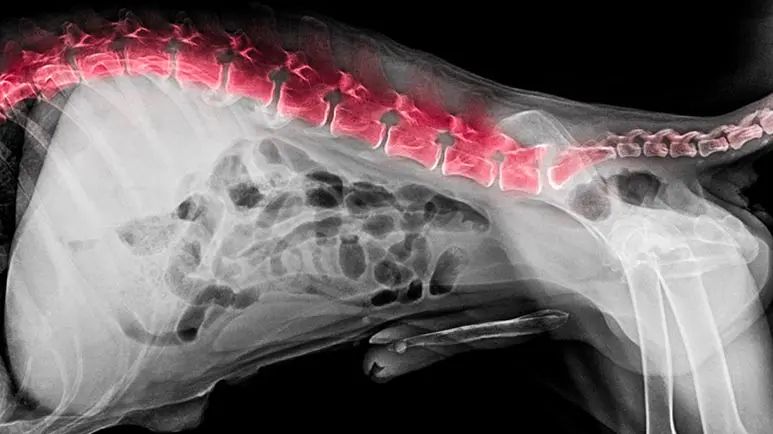

Your dog’s spine is made up of many small bones called vertebrae that run from the base of the skull all the way down the back to the end of the tail. These small bones are connected by cushiony, flexible discs made of cartilage — the intervertebral discs. The discs function as shock absorbers between each bone, and allow the neck, spine and tail to bend and flex as your dog changes positions.

Sitting above the discs and running through the vertebrae is the spinal cord, which consists of a mass of nerve fibers that send messages back and forth between the brain and the rest of the body.

The high cervical, mid thoracic, thoracolumbar, and lumbosacral regions are most commonly involved. Less often, the vertebral body itself can be the primary site of infection, in which case the condition is called spondylitis or vertebral osteomyelitis to distinguish it from DS.

Diskospondylitis causes inflammation (itis means inflammation), swelling, and bone deformities that put pressure on or compress the spinal cord that runs through the vertebrae of the back.